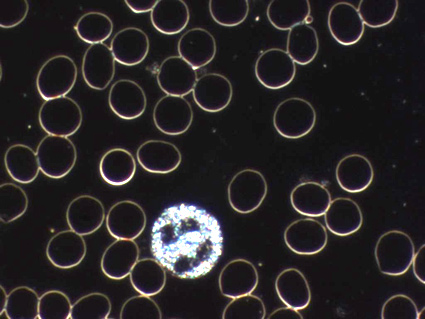

Dunkelfeldmikroskopie / Vitalblutanalyse

Haben Sie ihr vitales Blut schon einmal live auf einem Bildschirm angesehen, mit all seinen Bestandteilen? Dazu wird ein frisch entnommener Bluttropfen aus der Fingerbeere auf ein spezielles Dunkelfeld Mikroskop gelegt und bis zu 1000 fach vergr ert. Mittels einer Viodeo bertragung ist es so f r den Patienten anzusehen. Nach der Blutentnahme wird die Probe in regelm igen Abst nden bis zu mehreren Tagen untersucht und dokumentiert.

Dieses schon seit ber 250 Jahren bekannte Verfahren nach Prof. Dr. G nther Enderlein hat seit vielen Jahren meine Leidenschaft f r die Dunkelfeldmikroskopie erweckt und ist in meiner Praxis eine wichtige Untersuchung. Sie gibt auch f r den Patienten Aufschluss ber das innere Milieu, bis hin zu R ckschl ssen auf den Zustand der Organe. Die Untersuchung bezieht sich sowohl auf die Quantit t als auch auf die Qualit t der Blutzellen und des Plasmas. Prof. Enderlein pr gte den Begriff des Pleomorphismus, derzufolge sich Zellen, Bakterien, Viren ineinander umwandeln und in unterschiedlichen Erscheinungsformen auftreten k nnen. Da jedes dieser Kleinstlebewesen einen Stoffwechsel hat, kann dies dem Menschen schaden.

Hier ein kleiner Ausschnitt aus einem Tropfen Blut, 1000-fach vergr ert: